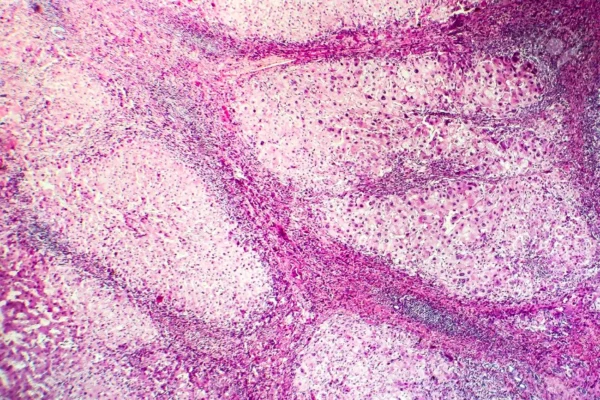

El proceso diagnóstico en anatomía patológica implica la identificación y evaluación de cambios anómalos en la estructura celular y tisular. La microscopía juega un papel central en este análisis, permitiendo la visualización detallada de las características patológicas. Además, se emplean técnicas avanzadas como la inmunohistoquímica y la biología molecular para proporcionar información adicional sobre la expresión de proteínas y la genética de las células.

La anatomía patológica moderna se basa en la comprensión de estas alteraciones celulares y moleculares que dan origen a las enfermedades. Los patólogos analizan las muestras de tejido y células para identificar las alteraciones morfológicas, estructurales y moleculares asociadas a enfermedades específicas. Esto permite un diagnóstico preciso y ayuda a comprender los mecanismos subyacentes de la enfermedad.